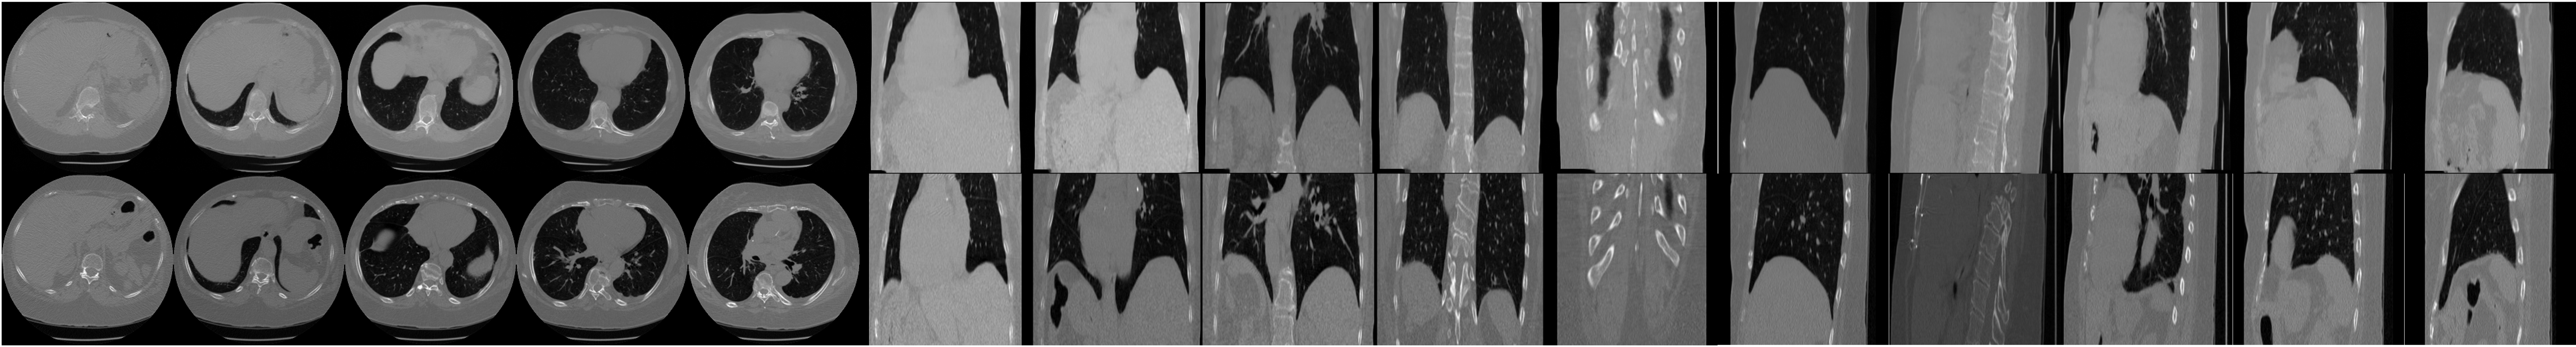

Our proposed method is able to learn a fully 3D prior on 256×256×256256\times 256\times 256 sized CT volumes, allowing it to generate high quality volumes. We used (7) with K=1K=1 and η=0.4\eta=0.4 and 200 steps for unconditional sampling. Figure 3 shows unconditional volume samples from LIDC-IDRI prior, visualized across axial, coronal, and sagittal slices. The top row shows slices from an unconditionally sampled volume, while the bottom row shows the nearest-neighbor volume from the training dataset. These results indicate that the proposed prior does not simply memorize from the training dataset and is capable of generating realistic high-resolution 3D CT volumes with fine-grained details of anatomic structure. Further generation results on different prior are in the appendix.

Refer to caption

Figure 3: Unconditional 3D image generation results using the LIDC-IDRI prior. The top row shows axial, coronal, and sagittal slices from a generated volume, and the bottom row shows the corresponding slices from its nearest-neighbor volume in the training dataset. The slice indices for the axial, coronal, and sagittal views are [30,80,130,180,230][30,80,130,180,230], [70,100,130,160,190][70,100,130,160,190], and [60,130,160,190,210][60,130,160,190,210], respectively